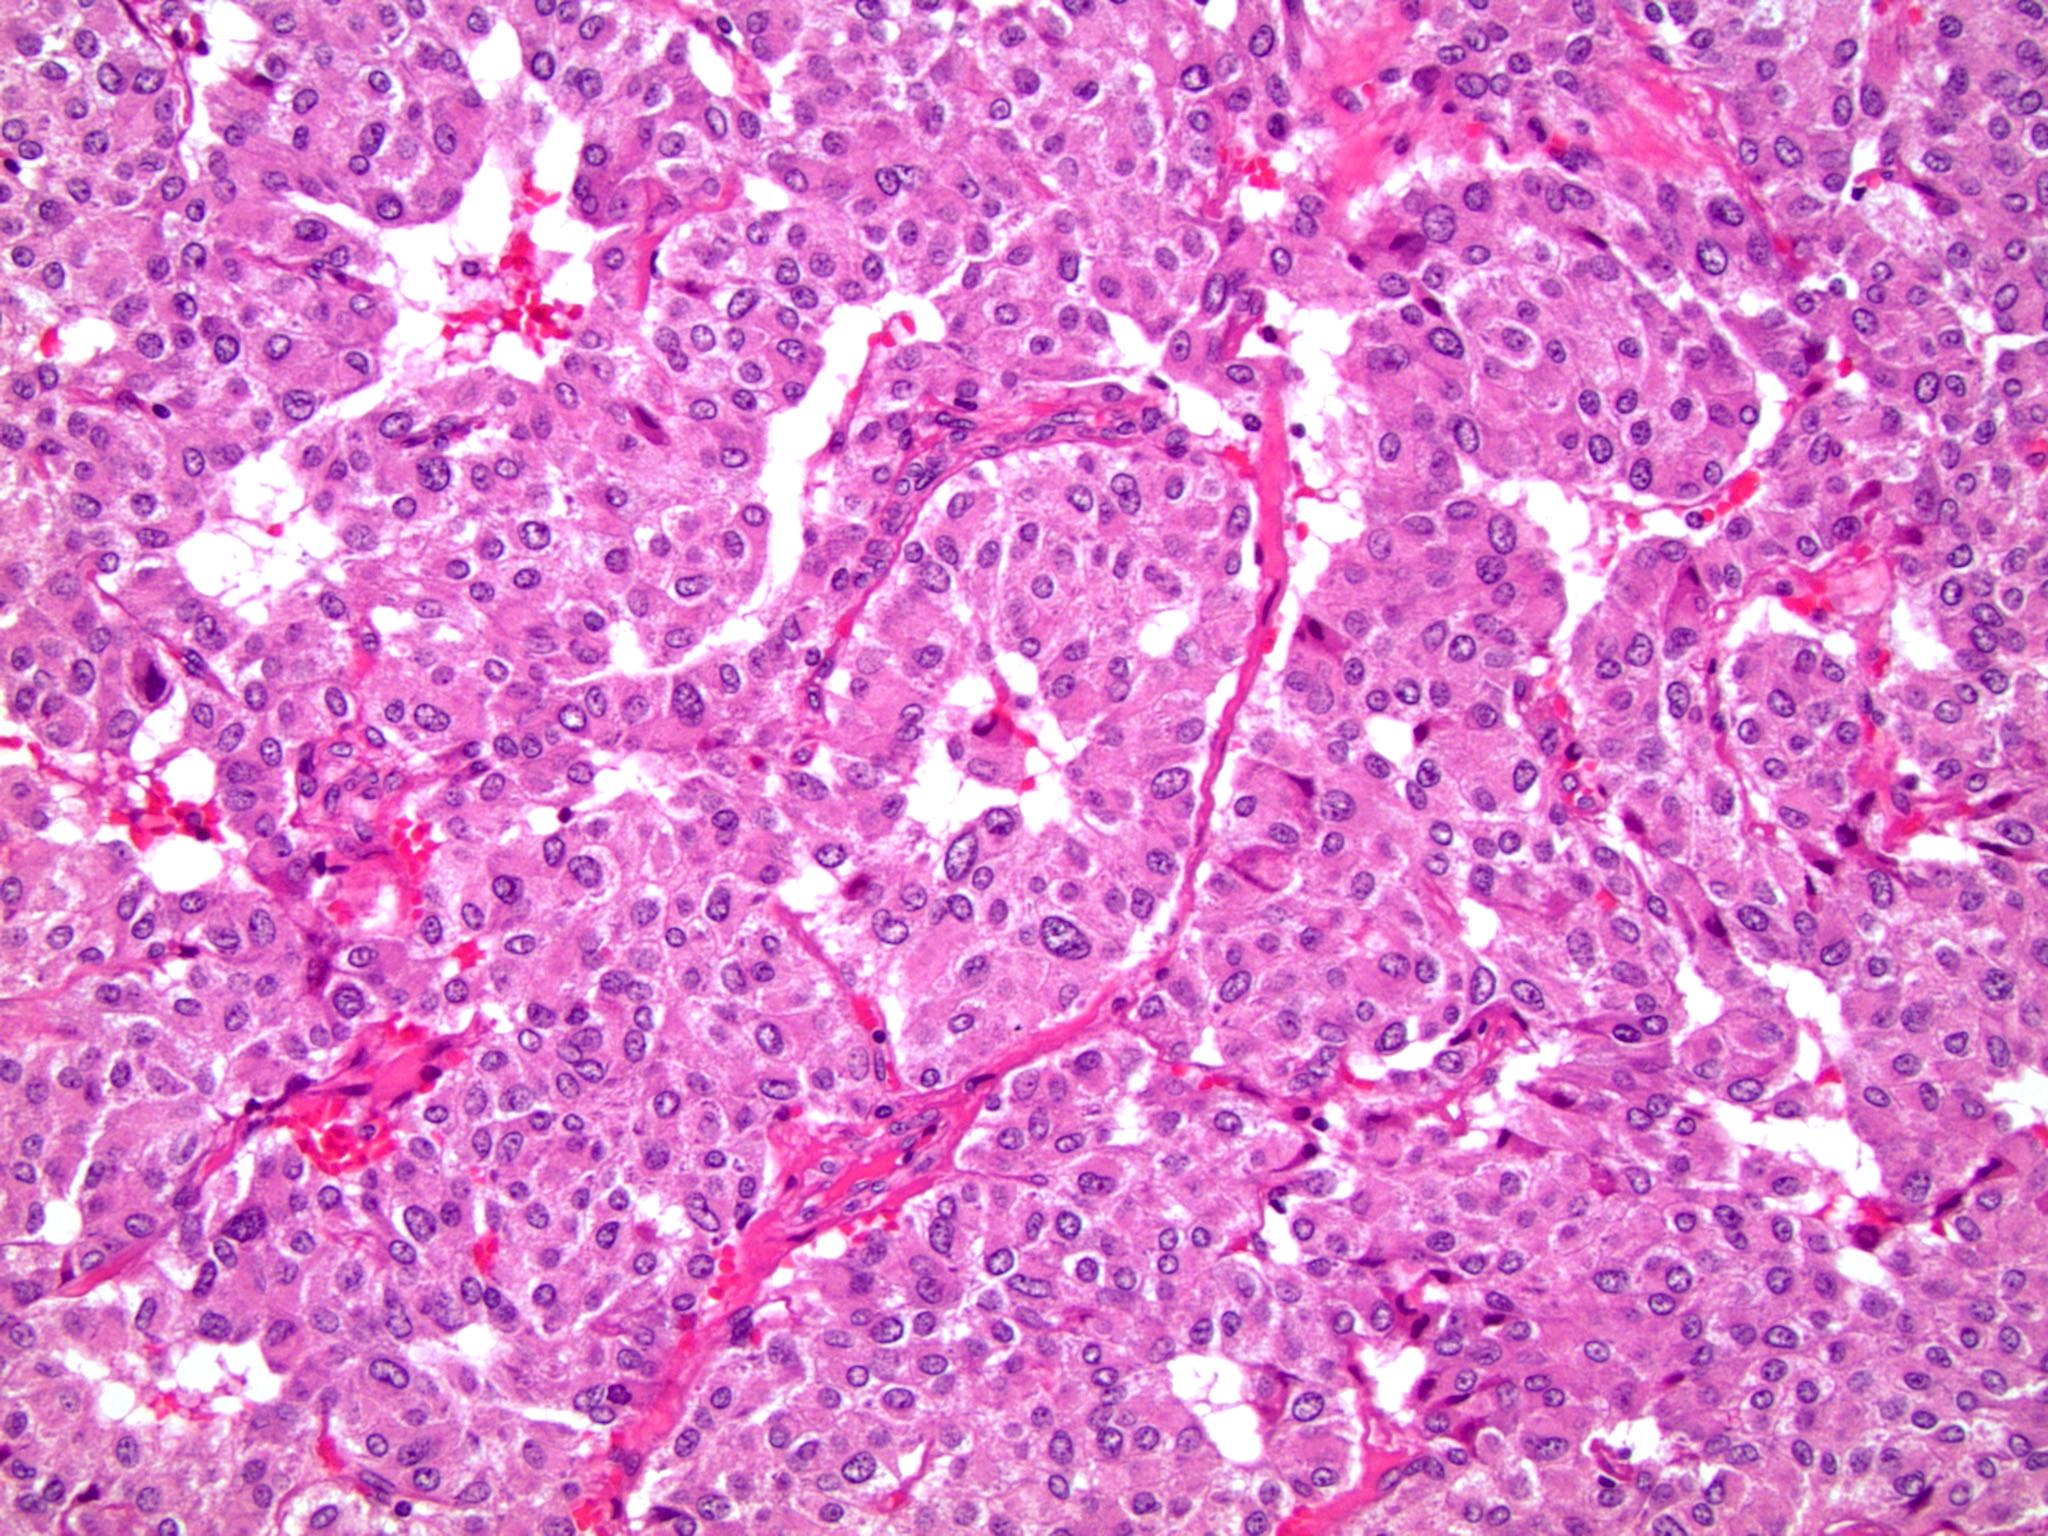

Microscopic (histologic) images

Contributed by Emily S. Reisenbichler, M.D., Andrey Bychkov, M.D., Ph.D., Maria Tretiakova, M.D., Ph.D. and Debra Zynger, M.D.

Positive staining - tumors

- Renal cell carcinoma, clear cell papillary type (76%) (Hum Pathol 2017;66:152), variable in chromophobe renal cell carcinoma (6 - 51%), less in oncocytoma (17 - 19%) (Hum Pathol 2014;45:244, Am J Surg Pathol 2014;38:13)